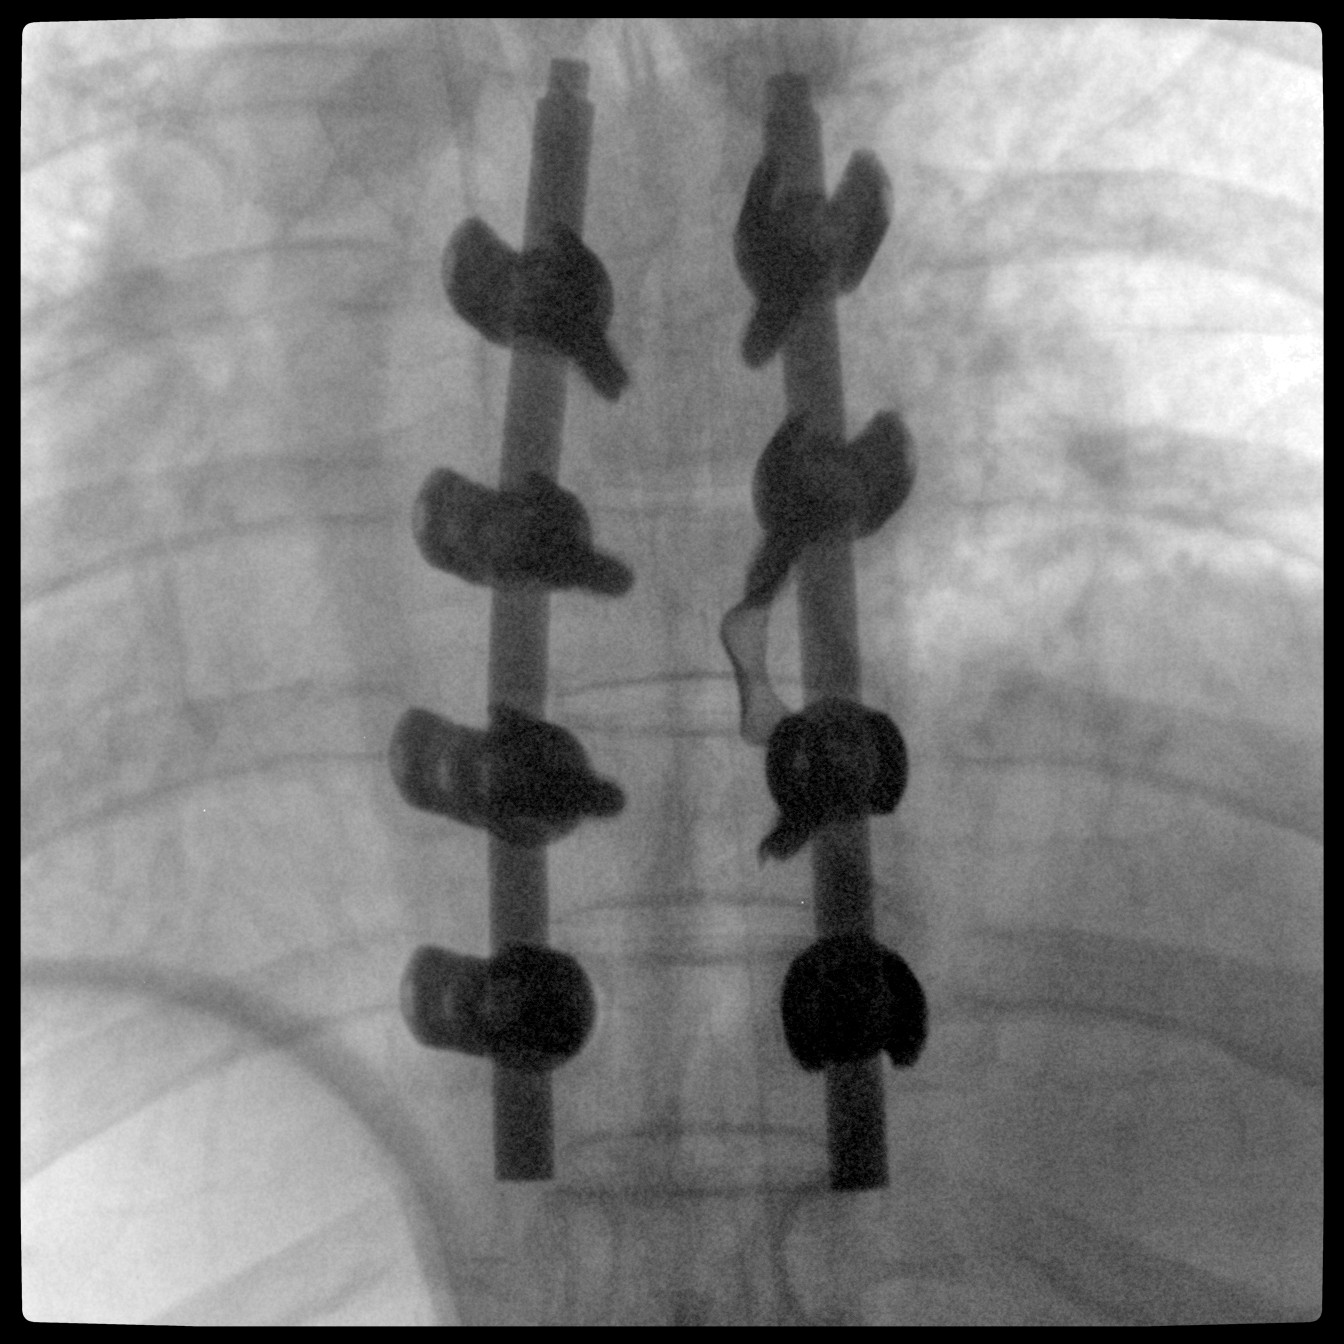

Clinical picture

臨床圖片